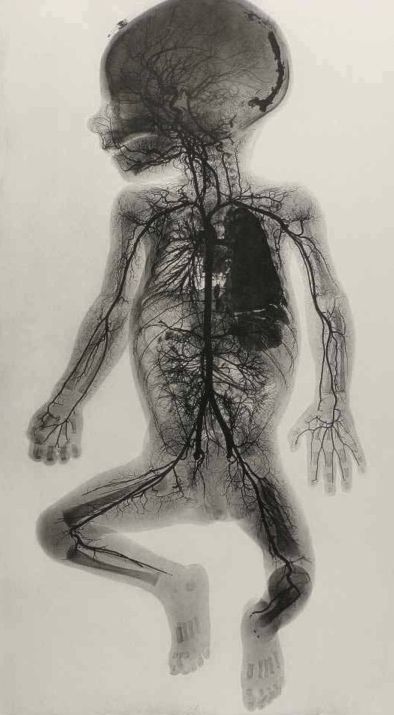

В некоторых случаях назначается МРТ головного мозга плода. Обычно это требуется в тех ситуациях, когда есть риск развития врождённых заболеваний. Специалисты способны сегодня достаточно точно определять состояние мозга в целом и различных сосудов в отдельности. Этот метод позволяет выявить степень повреждения тканей, а вместе с тем и развитие болезни в целом.

Лучше всего для исследований сосудов головного мозга у детей с помощью МРТ выбирать современные модели аппаратов. Напряжение магнитного поля 1,5 Тл позволяет получить наиболее чёткие изображения головного мозга. Благодаря этому врачи сразу видят даже мелкие родовые травмы, пороки развития и другие отклонения в работе мозга. На компьютерной модели сразу проявляются опухоли и повреждения структуры кровеносной системы.